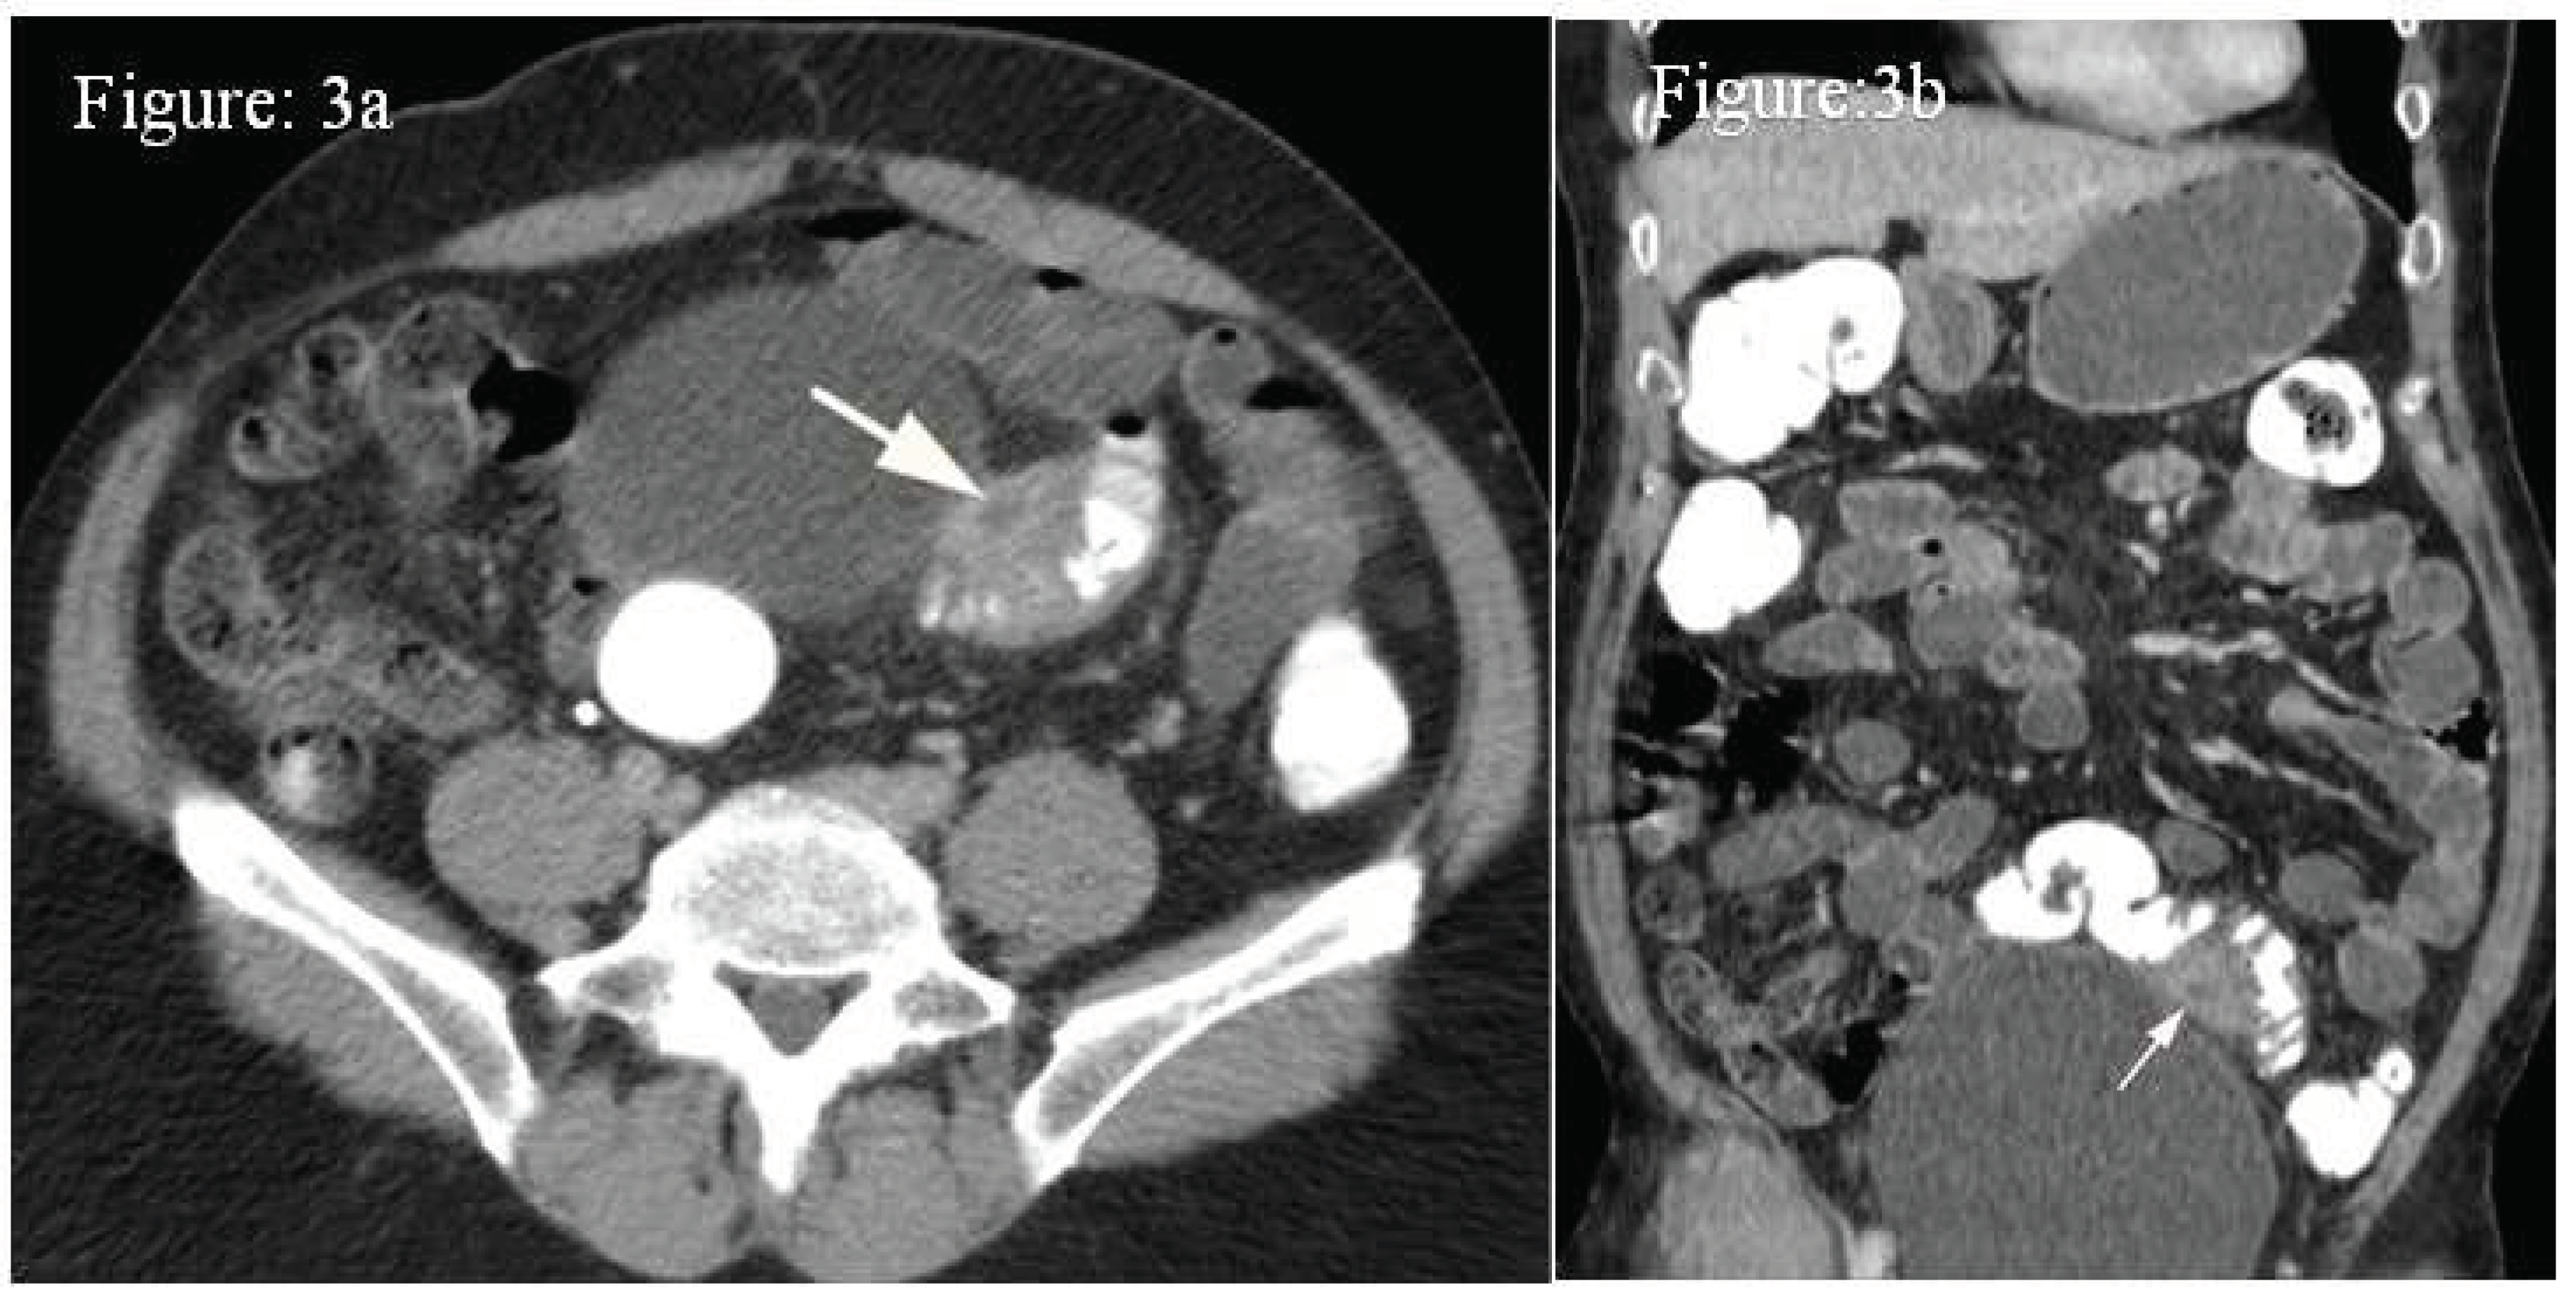

Case 2: